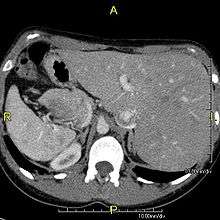

Situs inversus (also called situs transversus or oppositus) is a congenital condition in which the major visceral organs are reversed or mirrored from their normal positions. The normal arrangement of internal organs is known as situs solitus while situs inversus is generally the mirror image of situs solitus. Although cardiac problems are more common than in the general population, most people with situs inversus have no medical symptoms or complications resulting from the condition, and until the advent of modern medicine it was usually undiagnosed.

Situs inversus is found in about 0.01% of the population, or about 1 person in 10,000. In the most common situation, situs inversus totalis, it involves complete transposition (right to left reversal) of all of the abdominal organs. The heart is not in its usual position in the left chest, but is on the right, a condition known as dextrocardia (literally, right-hearted). Because the relationship between the organs is not changed, most people with situs inversus have no medical symptoms or complications, although they should wear a medical identification tag to warn emergency medical staff that the patient's internal organs are reversed from normal so they can act accordingly, e.g. by listening for a heartbeat on the right rather than left side of the chest.[1]

The condition affects all major structures within the thorax and abdomen. Generally, the organs are simply transposed through the sagittal plane. The heart is located on the right side of the thorax, the stomach and spleen on the right side of the abdomen and the liver and gall bladder on the left side. The heart's normal right atrium occurs on the left, and the left atrium is on the right. The lung anatomy is reversed and the left lung has 3 lobes while the right lung has 2 lobes. The intestines and other internal structures are also reversed from the normal, and the blood vessels, nerves, and lymphatics are also transposed.